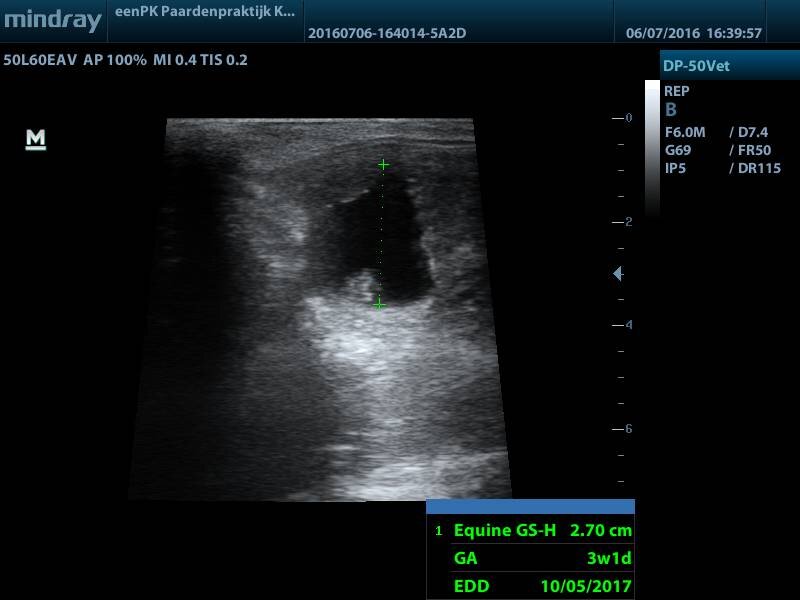

Yeeeeh, dat is 1! Dan gaan we door met Roza:

Drachtig! Het kortste van allemaal, maar wel goed zichtbaar.

Uitgerekend: 13-19 mei 2017